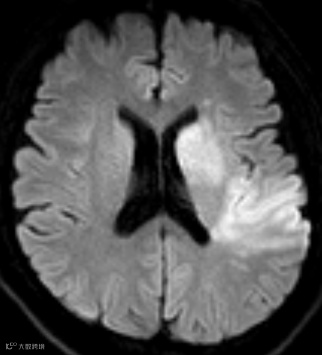

南京市第一医院是国家卫生健康委首批高级卒中中心,设有独立的神经内科急诊及脑血管病绿色诊疗通道。接诊的侯建康主治医师第一时间启动绿通,完善了头部磁共振及血管成像检查,明确了王先生急性缺血性脑梗死的诊断,而梗死原因是王先生脑内两根非常重要的血管(左侧颈动脉和左侧大脑中动脉)发生了堵塞。

手术过程中,侯建康主治医师发现了王先生血管堵塞的前因后果:左侧颈动脉形成了动脉夹层,夹层进一步诱发血栓形成;而形成的血栓被血流冲刷脱落,进一步堵塞了远端的大脑中动脉。在施洪超主任医师指导下,侯建康主治医师使用抽吸导管将脱落到大脑中动脉的血栓抽吸了出来,随后在动脉夹层的部位植入了一枚支架以重建管腔。